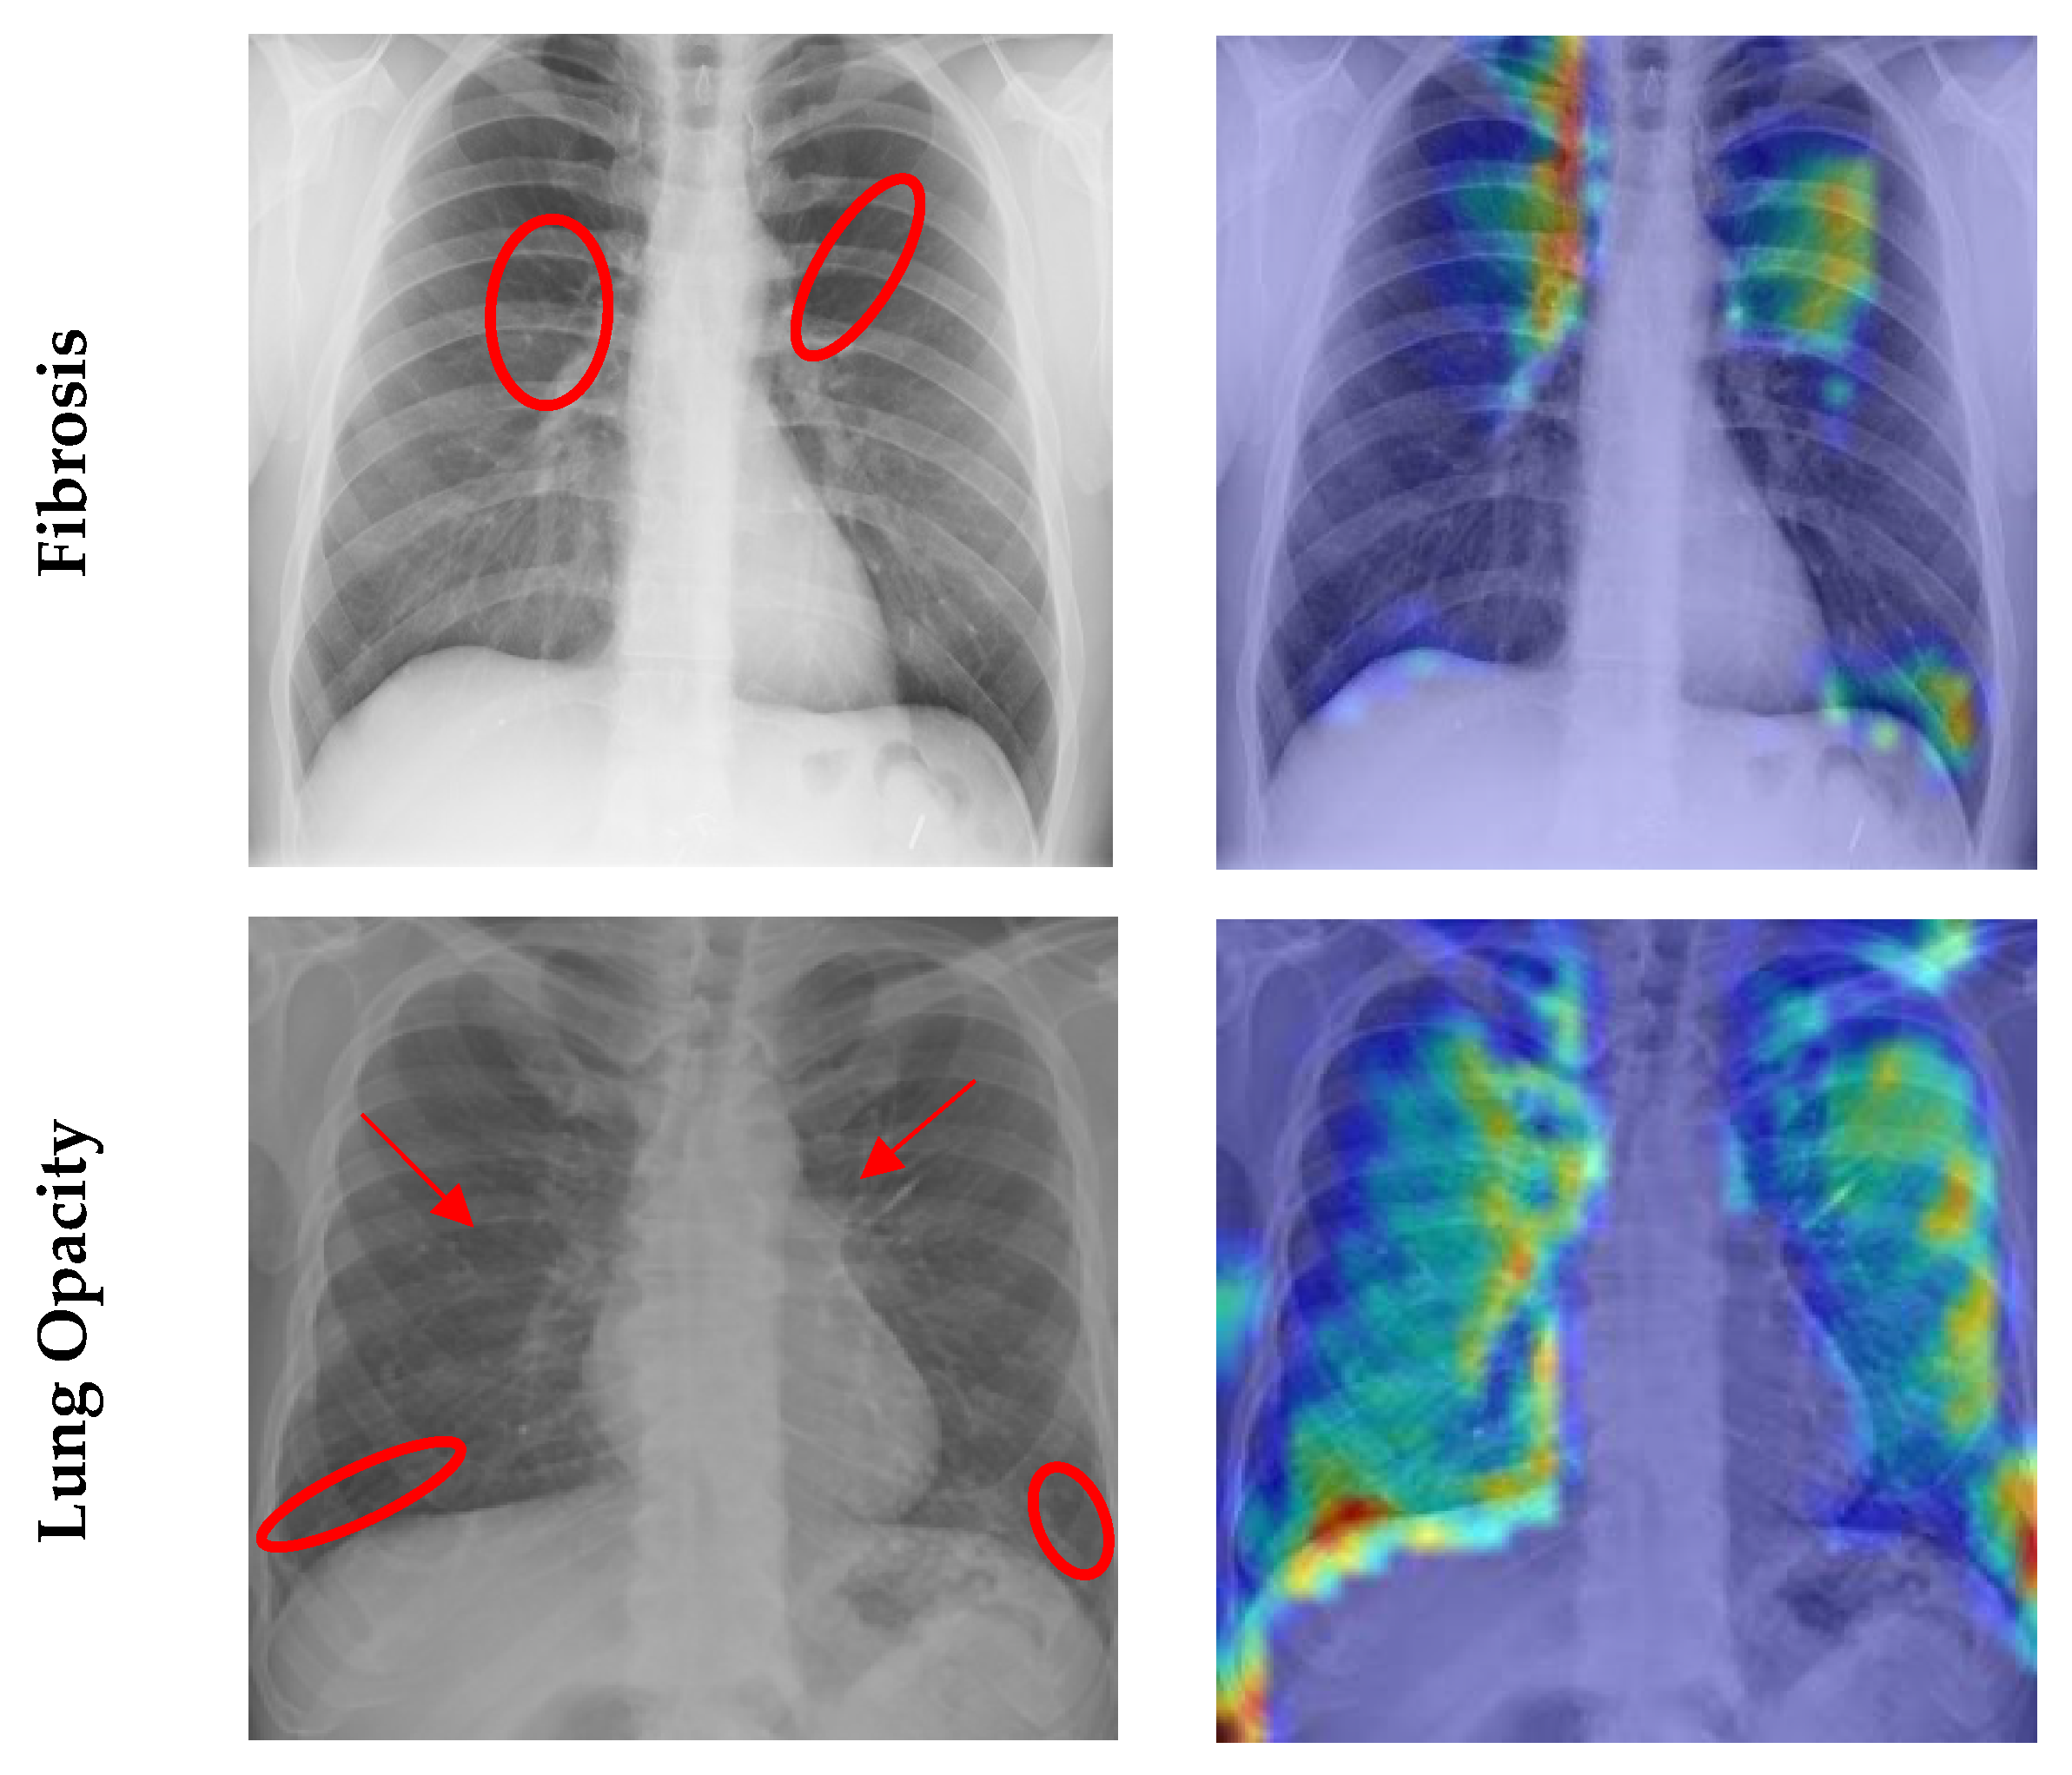

4.7. Grad CAM Visualisation

- Selvaraju, R.R.; Cogswell, M.; Das, A.; Vedantam, R.; Parikh, D.; Batra, D. Grad-cam: Visual explanations from deep networks via gradient-based localization. In Proceedings of the IEEE International Conference on Computer Vision, Venice, Italy, 22–29 October 2017; pp. 618–626. [Google Scholar]